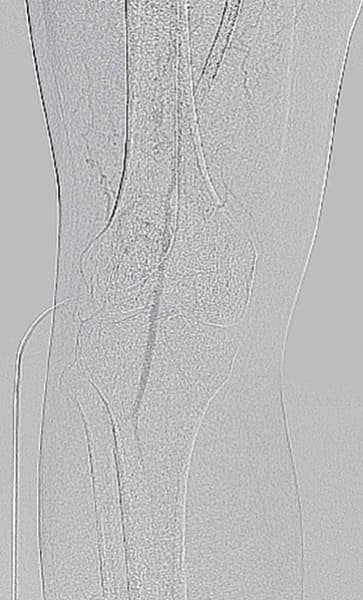

- ステント近位端は非常に硬化しており、0.014 inch wireでのknuckle wiringおよび0.035 inch wire のtail 側でもステント内へ進入できず

- 4 Fr IMA造影カテーテルにマイクロカテーテル併用下でtapered coil typeの0.018 inch wireにてなんとかステント近位端を通過(図2)

- ステント近位端のみではなく、遠位端やBMSとDESとの重複留置部の硬化が強く難渋したが、なんとか閉塞病変を通過(図3)